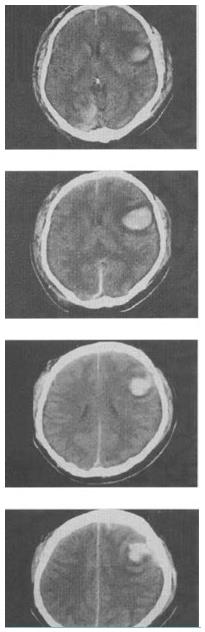

女,52岁,有高血压病史,半小时前突感头晕,剧烈头痛,CT检查如图,最可能的诊断为()。

A、脑梗死

B、脑出血

C、脑膜瘤

D、转移瘤

E、胶质瘤

正确答案:

B